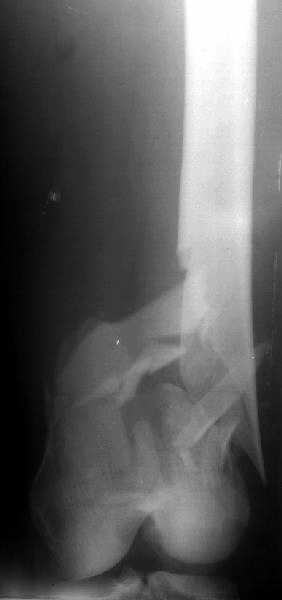

Отправитель: Alexander Chelnokov 27 Декабрь 2003, 21:34

Sorry but I've just prepared postop images - attached. A solid 13 mm nail was used. A few degrees of recurvation appears to be which i missed on image intensifier. I'm still uncertain about

advantages/disadvantages of ante/retrograde nailing for such fractures.